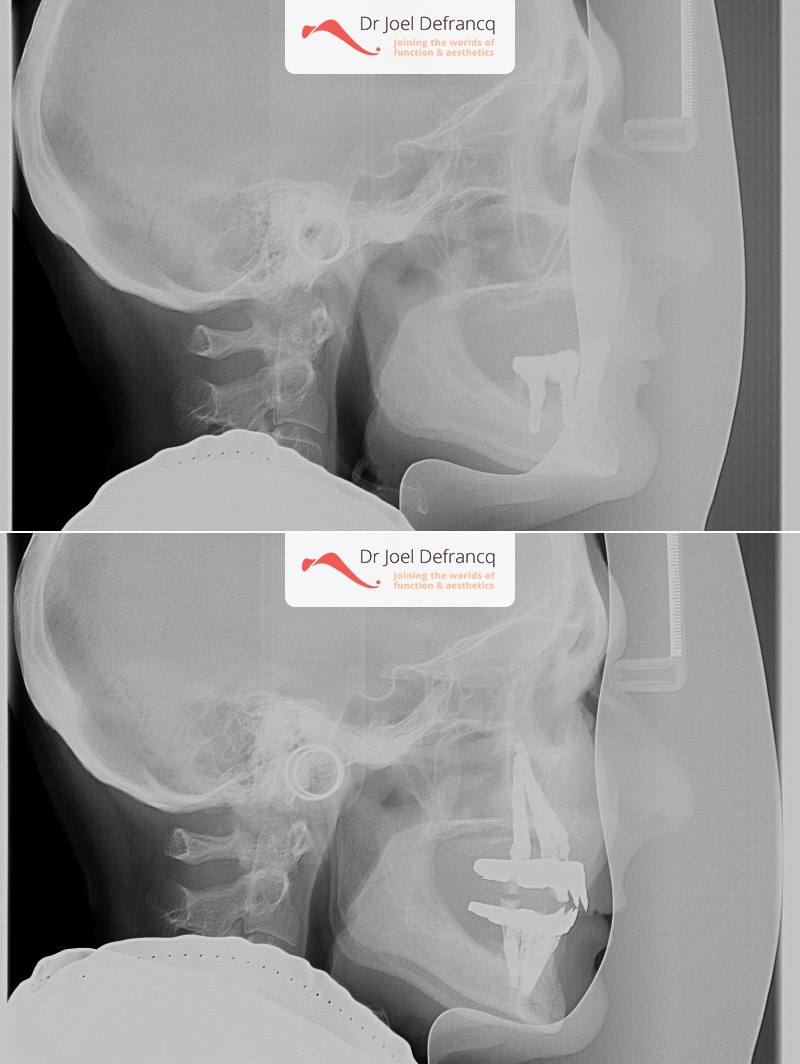

Bessina: "all on four " dentale implantaten

Behandeling tandheelkundige implantaten

- Vaste tanden op implantaten (bovenkaak)

- Vaste tanden op implantaten (onderkaak)

- Zygoma implantaten